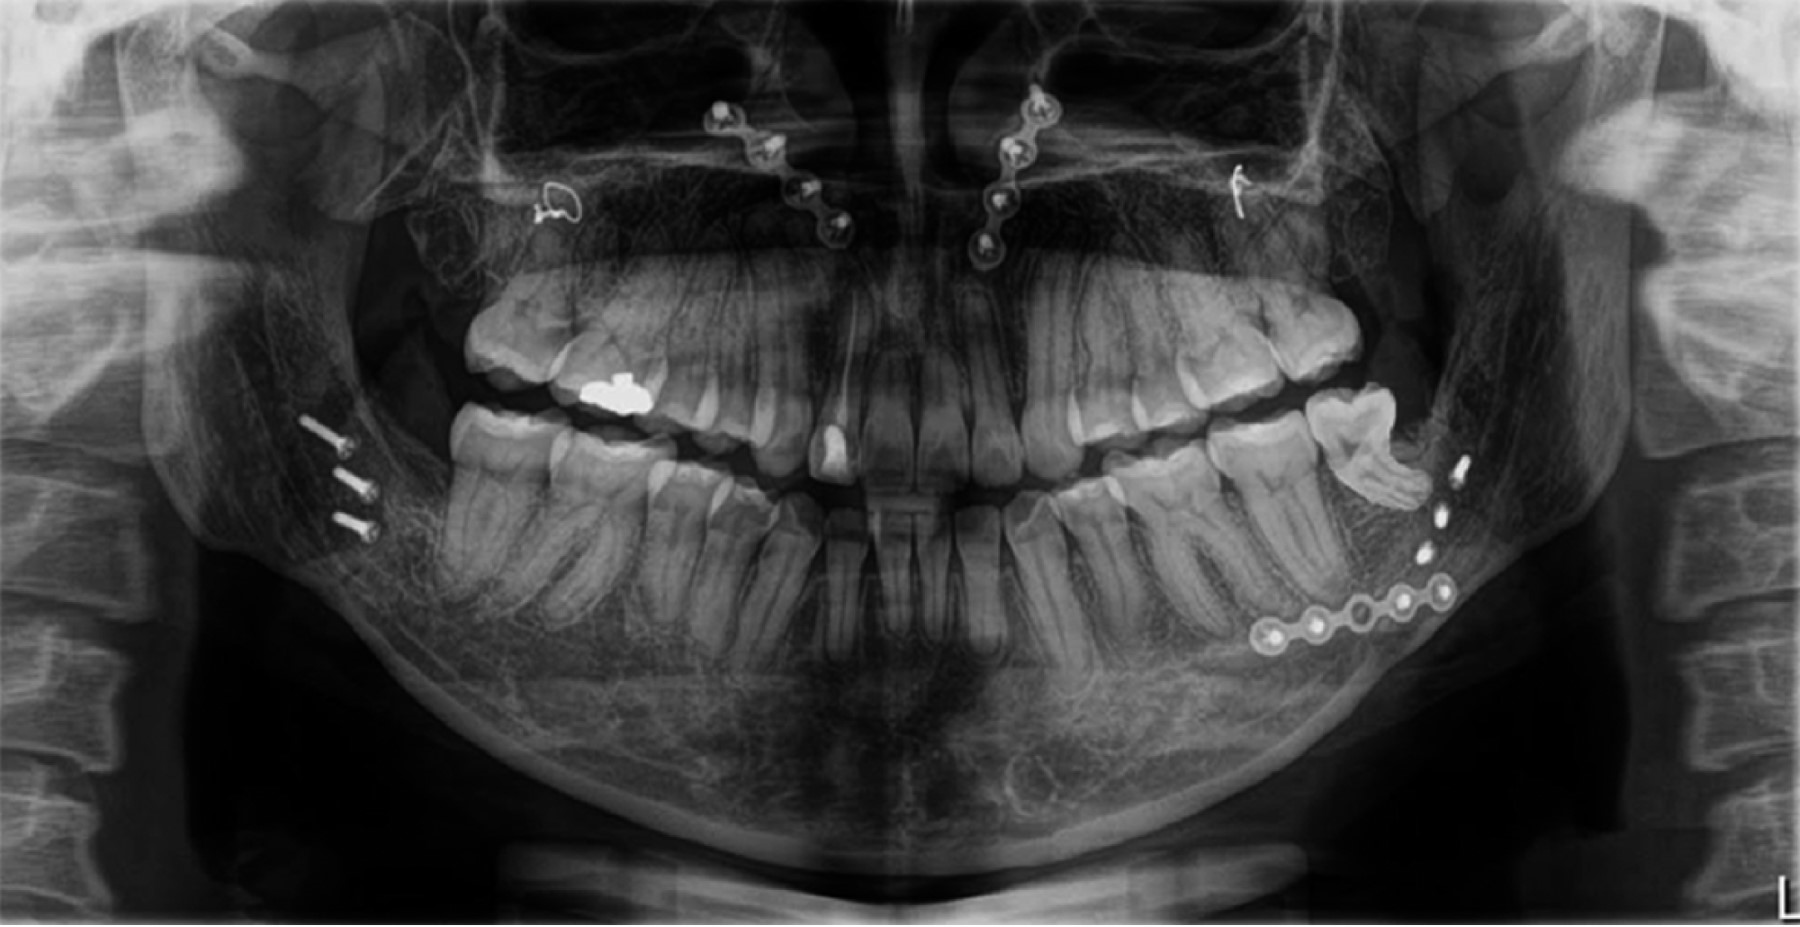

De acuerdo con la evaluación de los estudios radiográficos (Figuras 3 y 4), fotografías extra- e intraorales y datos cefalométricos (Tabla 1) se decide realizar tratamiento ortodóncico-quirúrgico y de esta manera cumplir con los objetivos planeados.

Fase prequirúrgica: cementación de brackets CCO slot 0.022" × 0.028", iniciando con arcos NiTi 0.014" en ambas arcadas para comenzar con la alineación y nivelación. El tratamiento continuó con arcos 0.016" NiTi, 0.016" × 0.022" NiTi, 0.019" × 0.025" NiTi, 0.019" × 0.025" acero.

Al cabo de 18 meses se revaloró el caso con estudios radiográficos y modelos de estudio junto con el Departamento de Cirugía Oral y Maxilofacial y se programó la cirugía ortognática. Se colocaron arcos quirúrgicos previos a la cirugía, arco 0.019" × 0.025" de acero inoxidable con ganchos quirúrgicos. La primera fase del tratamiento constó de 20 meses.

Fase quirúrgica: se determinó realizar cirugía bimaxilar, en el maxilar superior se realizó una osteotomía Le Fort tipo 1 alta por la hipoplasia del tercio medio que presentaba el paciente, se realizó un avance maxilar de 4 mm y una intrusión maxilar de 6 mm en anterior y 5 mm en posterior. En la mandíbula se realizó una OSRAM (osteotomía sagital de rama), con anterorrotación mandibular. La segunda fase constó de tres semanas, desde la cirugía hasta la primera cita postquirúrgica, previa recuperación.